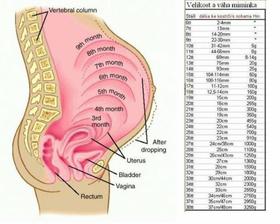

4/04/2009 dalsia kontrola u lekara, 18 tyzden a 1 den, (54kg) brusko 18cm, vsetko v poriadku

2/05/2009 kontrola u lekara, 22 tyzden a 1 den, (55,5kg) brusko 21cm, vsetko v poriadku

6/06/2009 kontrola u lekara, 27 tyzden a 1 den, (60kg) brusko 26 cm, vsetko v poriadku

16/07/2009 kontrola u lekara, 32 tyzden a 6 den, (62kg) brusko 33cm, merania maleho su v poriadku, krcok maternice nie je uplne zatvoreny - najblizsie 3 tyzdne mam vela oddychovat...

4/08/2009 posledna kontrola u mojho lekara pred odstahovanim sa ☹ 35 tyzden a 4 den, (63kg) brusko 35 cm, maly sa posunul uz do dolnej casti panvy, krcok je opat dost makky, mam vela oddychovat...podla lekara sa maly narodi skor - v polovici augusta, tak uvidime!

29/08 kontrola u noveho lekara po prestahovani, 39 tyzden a 1 den, je surovy :( co uz! do ciela nam chyba uz len kusok, tak snad to uz dotiahneme do uspesneho konca 🙂 Krcok maternice je uz otvoreny na dva cm, podla lekara sa porod moze spustit tento tyzden. V piatok mam dalsiu kontrolu - ak dovtedy neporodim. Dnes bol tlak ok, brusko 38cm, vaha 64kg